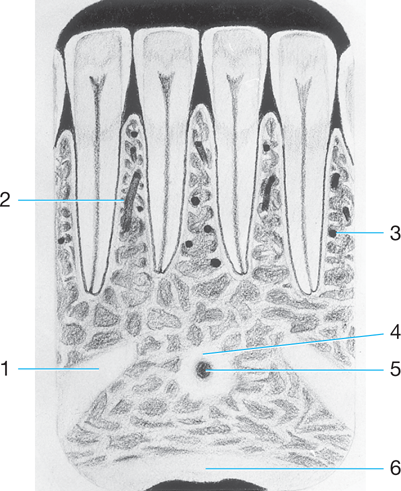

PDL space

1.

Dental base